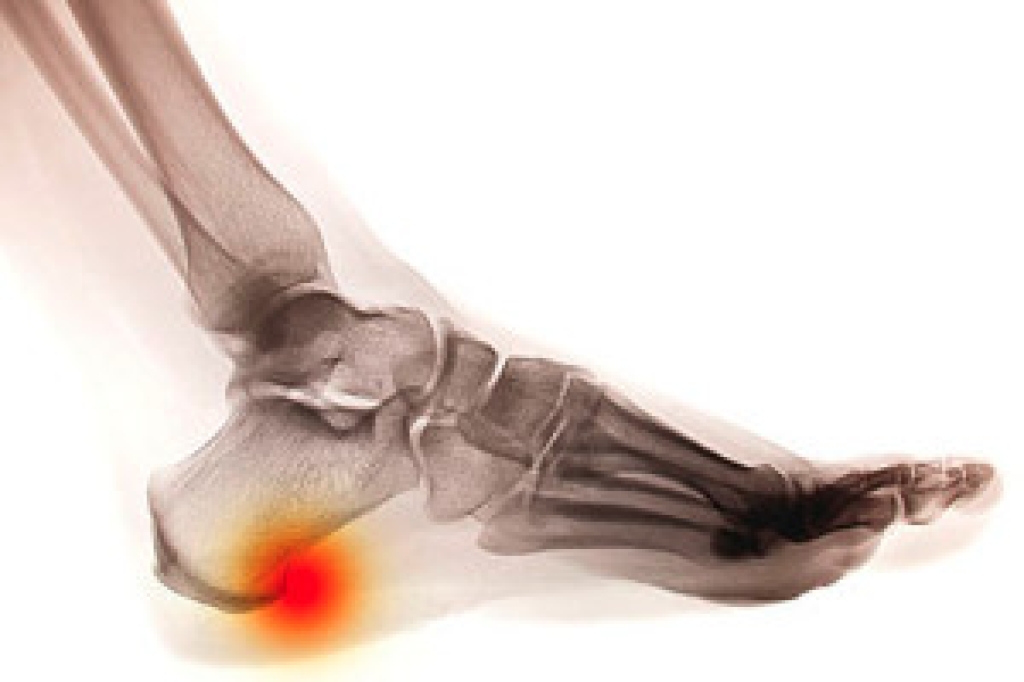

Ankle and foot injuries are common among athletes and in many sports. They can be caused by several problems and may be potentially serious. If you are feeling pain or think you were injured in a sporting event or when exercising, consult with Dr. Robbi Young from Grand Haven Foot & Ankle. Our doctor will assess your condition and provide you with quality foot and ankle treatment.

The most common injuries that occur in sporting activities include:

- Achilles Tendonitis

- Achilles Tendon Rupture

- Ankle Sprains

- Broken Foot

- Plantar Fasciitis

- Stress Fractures

- Turf Toe

Symptoms vary depending upon the injury and in some cases, there may be no symptoms at all. However, in most cases, some form of symptom is experienced. Pain, aching, burning, bruising, tenderness, tightness or stiffness, sensation loss, difficulty moving, and swelling are the most common symptoms.

Just as symptoms vary depending upon the injury, so do treatment options. A common treatment method is known as the RICE method. This method involves rest, applying ice, compression and elevating the afflicted foot or ankle. If the injury appears to be more serious, surgery might be required, such as arthroscopic or reconstructive surgery. Lastly, rehabilitation or therapy might be needed to gain full functionality in the afflicted area. Any discomfort experienced by an athlete must be evaluated by a licensed, reputable medical professional.